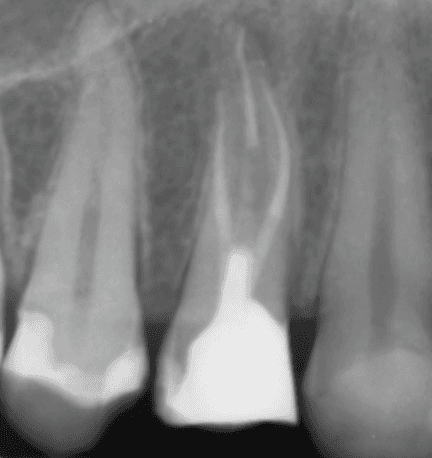

KREENA'S CASES